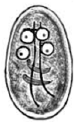

Em um exame parasitológico de rotina, foram visualizados diversos indivíduos do parasito apresentados a seguir. Podemos concluir que o paciente apresenta

ascaridíase.

amebíase.

giardíase.